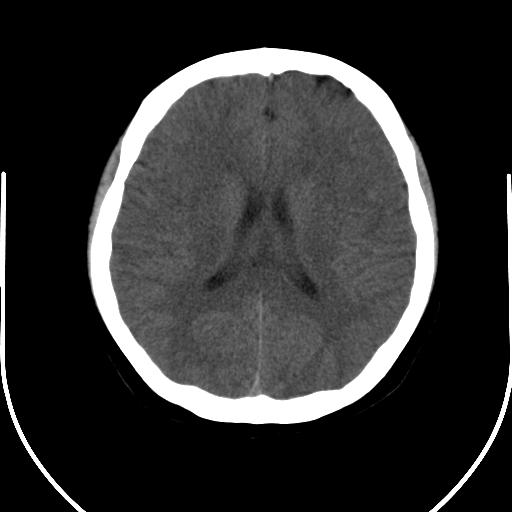

以下是引用mlxq3086在2007-8-27 13:35:00的发言:[br]单凭平扫无法诊断,请结合增强了解!